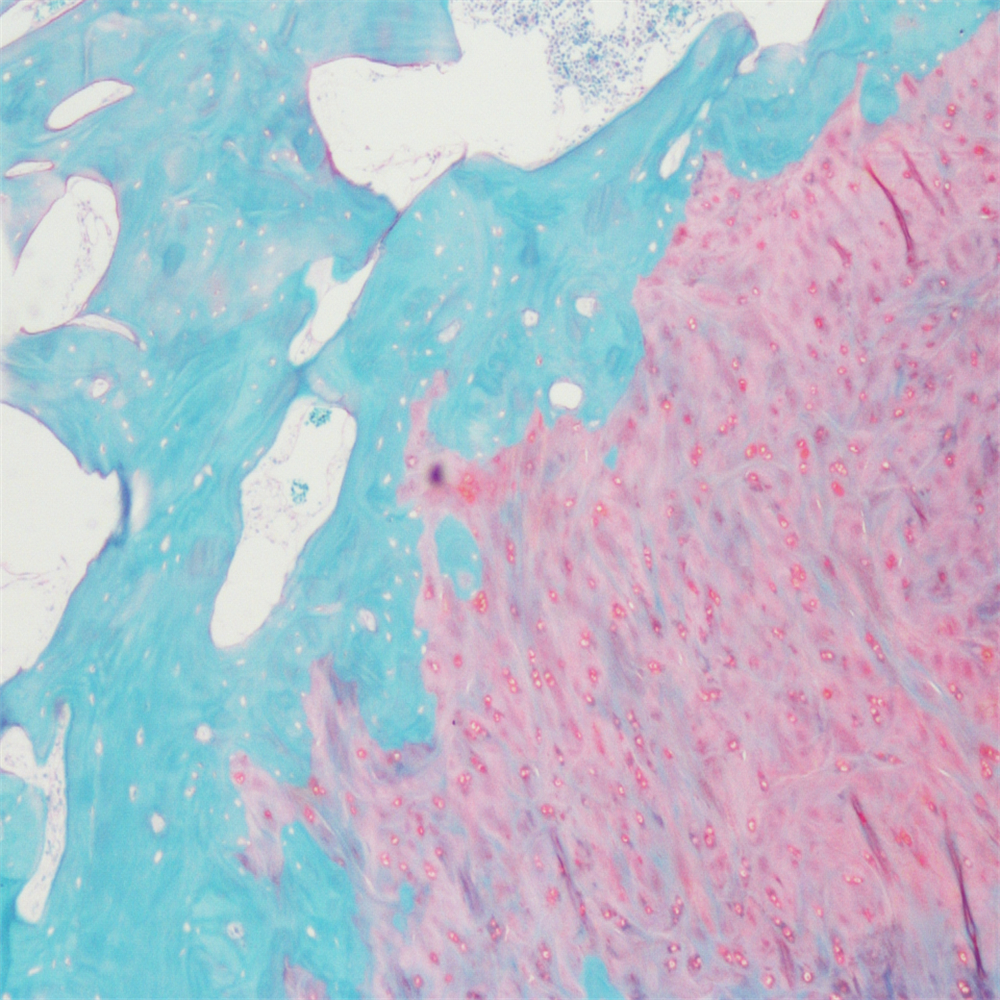

番红-固绿染色

在关节软骨及软骨下骨相关形态学研究中,常需联合多种染料以清晰显示组织学结构。其中,始于20世纪60年代的番红O(safranin O)-固绿(fast green)染色法,因能直观呈现关节软骨、软骨下骨及骨组织的形态结构而被广泛应用。该染色法可使软骨呈红色,成骨组织呈绿色。

番红-固绿(软骨)染色法的核心原理的是:嗜碱性的软骨组织可与碱性染料番红O结合,呈现红色;嗜酸性的骨组织则与酸性染料固绿结合,呈现绿色或蓝色,与红色软骨形成鲜明对比,从而实现软骨组织与骨组织的清晰区分。

番红O属于可结合多阴离子的阳离子染料,其对软骨组织的显色机制是阳离子染料与多糖中的阴离子基团(如硫酸软骨素、硫酸角质素)发生结合。番红O的着色深度与阴离子浓度大致成正比,可间接反映基质中蛋白多糖的含量及分布情况。当软骨受损时,软骨内糖蛋白会释放,导致基质成分分布不均,进而使番红O染色变浅或无着色。借助图像分析软件,可对番红O染色的软骨基质进行定量分析。固绿可与胶原纤维牢固结合,且不易褪色。

<番红固绿-骨>